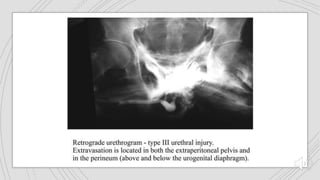

URETHRALTRAUMA

 Almost entirely restricted to males unless there is major

pelvic trauma in females.

 Should be suspected

 Pelvic trauma associated with hematuria or retention.

 Especially blood at the urethral meatus.

URETHRALTRAUMA  Almost entirelyrestricted to males unless there is major pelvic trauma in females.  Should be suspected  Pelvic trauma associated with hematuria or retention.  Especially blood at the urethral meatus.

FINDINGS Rupture Partial : contrastextravasation with some filling of proximal urethra Complete : failure of filling of proximal urethra Stricture (usually <1cm or so in length).